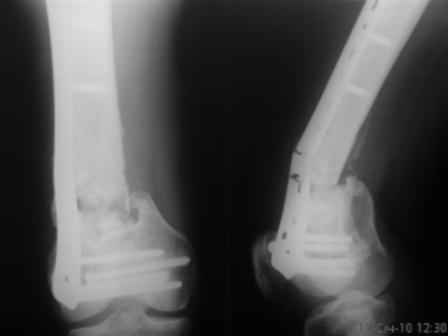

Больной, 30 лет, высокоэнергетическая травма 6 мес назад (базальный перелом шейки бедра + перелом дистального метаэпифиза бедра на той же ноге по типу 33-С2). Практически сразу же был произведен МОС шейки системой DHS (Synthes), через две недели - МОС дист.отдела бедра системой LISS (Synthes)плюс костная пластика с крыла подзвдошной кости.

На сегодняшний день наступил перелом пластины, укорочение бедра 2 см. Перелом шейки клинически и рентгенологически сросся. Больной астеничен, немного анемичен. Рентгенограммы прилагаются.